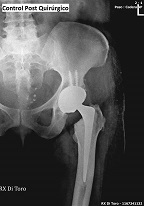

Utilizamos sensores Flat Panel, que nos permiten acortar al Máximo el tiempo de exposición (Dosis de Radiación) y obtener la adquisición inmediata de las imágenes.